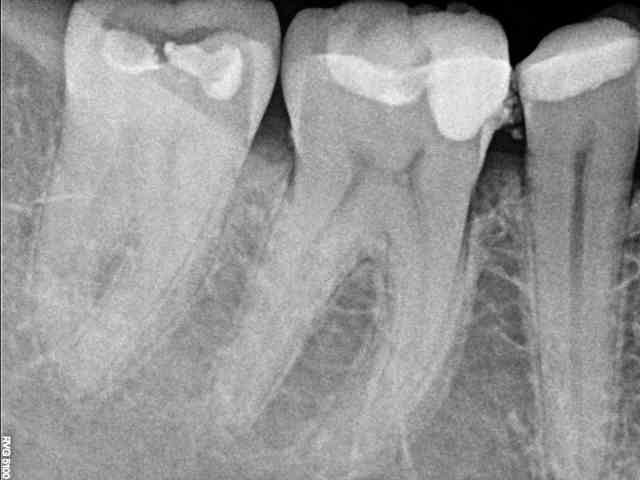

Zdjęcie punktowe

to precyzyjne badanie radiologiczne wykonywane w celu oceny jednego konkretnego zęba lub jego najbliższego otoczenia. Pozwala ono na bardzo dokładne zobrazowanie korony, korzenia zęba, ozębnej oraz kości wokół wierzchołka korzenia.